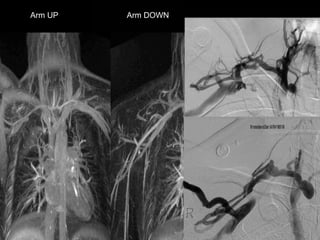

MRA for TOS: Blood Pool MRA

• Anatomic imaging: Oblique sag and cor T1/T2

• Relaxed and Challenged imaging:

§ Gadofosveset (blood pool agent)

§ Breath-hold FSPGR, ECG-gated, high resolution (1.8

mm ST, 448 x 448 matrix) CORONAL acquisition

§ Challenged: Arm Abducted

§ Relaxed: Arm Down

Arm UP Arm DOWN